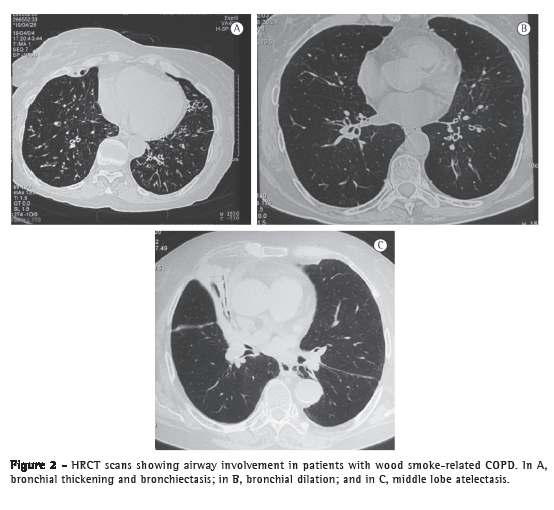

The emphysema scores, expressed as median (interquartile range), were significantly lower in the wood smoke-related COPD group than in the smoking-related COPD group-0 (0-1) vs. 92.5 (73-103); p < 0.001; Figure 1-and the airway involvement was greater in the former: peribronchial thickening (75% vs. 10%; p = 0.008) and bronchial dilation (67% vs. 10%; p = 0.024). In addition, tree-in-bud and subsegmental atelectasis were observed in women with wood smoke-related COPD (in 25% and 33%, respectively), as was severe wall thickening in large bronchi, none of which were found in those with smoking-related COPD (Figure 2). No mosaic pattern was observed on the slices obtained during exhalation in any patient. The agreement between the initial readings and the consensus readings for emphysema assessment was very good, with a concordance correlation coefficient of 0.937 (p < 0.001), a mean difference of 0.030 ± 15.7 between the scores obtained by the two methods of assessment, and Bland & Altman limits of agreement of −30.77 and 30.83.

In this study based on chest HRCT findings, we demonstrated that, unlike women with smoking-related COPD, those with wood smoke-related COPD and severe obstruction do not have emphysema, although they have significant airway involvement manifesting as peribronchial thickening, bronchial dilation, and subsegmental atelectasis. These findings correlated with the fact that the change in DLCO and in the DLCO/VA ratio, as determined by pulmonary function tests, was smaller in women with wood smoke-related COPD than in those with smoking-related COPD, a finding that has been described in cases of severe small airways involvement and little emphysema.(10)

The tomographic findings confirmed the absence of significant emphysema in women with wood smoke-related COPD and showed moderate emphysema in women with smoking-related COPD. Previous studies have demonstrated that this subjective quantification of emphysema on HRCT scans correlates significantly with pathologic grading of emphysema on the basis of microscopic examination of resected lung specimens.(19,20) Although this subjective quantification might have disadvantages, such as overestimation of the degree of emphysema and, sometimes, low agreement among different observers,(21) we believe that the technique used in our study was adequate, considering the clear differences found between the two groups and the good agreement observed between the individual readings by the three observers and the consensus readings. Therefore, our results are highly reproducible. As indicated earlier in this article, women exposed to wood smoke, in addition to not having emphysema, were found to have peribronchial thickening, bronchiolar and bronchial dilation, and subsegmental atelectasis, which are evidence of significant airway involvement. The presence of atelectasis is a common finding in individuals with wood smoke-related COPD and has been correlated with endoscopic and histological findings of anthracosis and bronchial inflammation.(9,22)

In conclusion, in female patients with severe wood smoke-related COPD, HRCT scans showed no significant emphysema, the main finding being severe airway involvement manifesting as peribronchial thickening, bronchial dilation, and subsegmental atelectasis. The reduction in DLCO and VA, with a normal DLCO/VA ratio, is due to severe bronchial obstruction and maldistribution of inspired gas during the determination of single-breath DLCO. We believe that the airflow obstruction in these patients is mainly caused by severe airway involvement rather than by a loss of elastic recoil due to emphysema, a finding that contributes to the understanding of COPD and indicates that pathophysiologically distinct diseases with one shared clinical manifestation (airflow obstruction), which might depend on the type of irritant or contaminant, are being included under the designation of COPD.